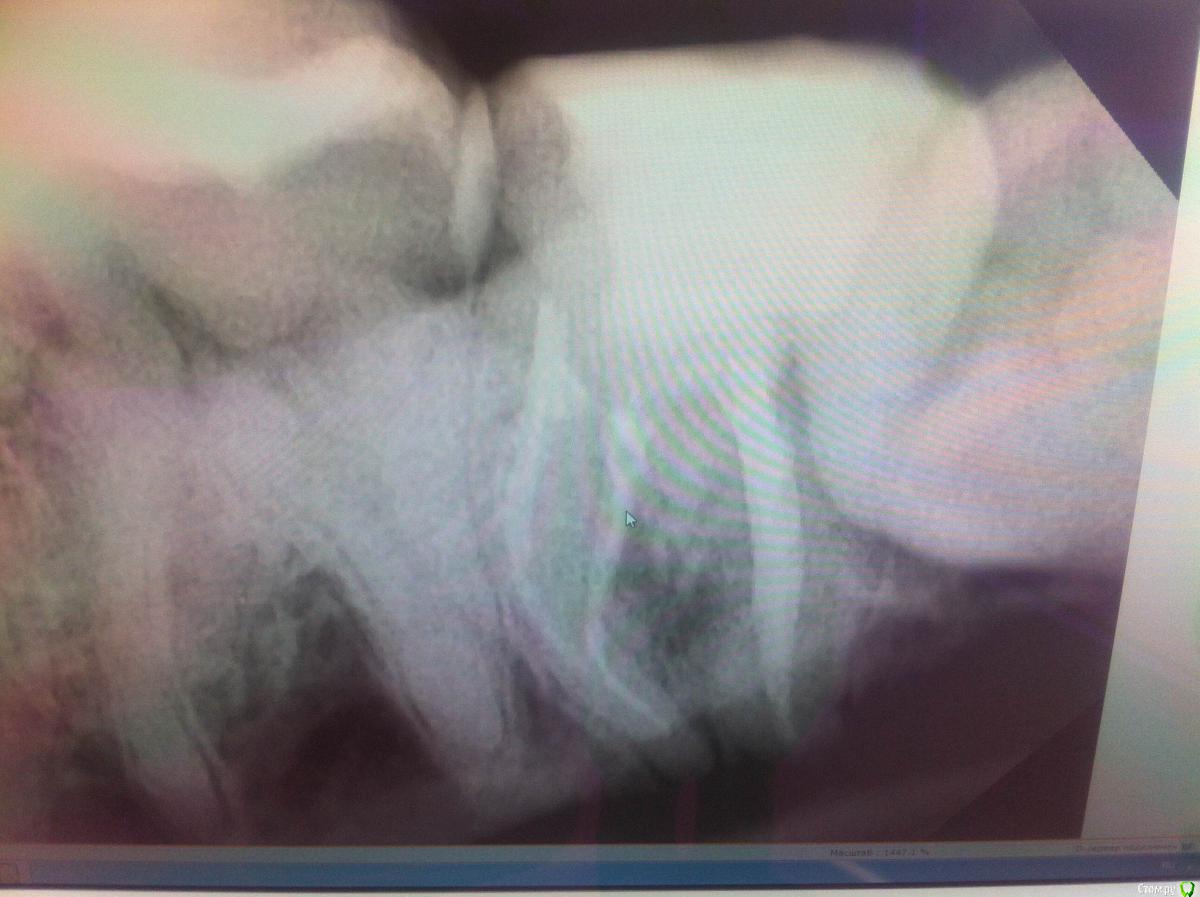

yaDaniel Опубликовано 13 марта, 2017 Поделиться Опубликовано 13 марта, 2017 (изменено) Доброго времени суток. Обратился к стоматологу с ноющей болью, диагностировали пульпит, Наложили мазь и поставили временную пломбу, через неделю удалили нервы и запломбировали зуб. Через месяц зуб начал реагировать на горячее, потом начал иногда беспокоить ( время от времени ноющая легкая боль). Мой стоматолог отправил меня к другому специалисту (коллеге) в другую клинику. Там мне сделали снимок, его я приложил. Врач довольно долго возилась с зубом( точно не знаю, что она делала) в итоге наложила мазь и поставила пломбу. Мне сказали, что кореневая система моего зуба, очень сложная, имеет два изгиба, вылечить такой зуб очень сложно. Если в течении 10 дней зуб будет беспокоить, то надо его удалять. Если нет, ждать еще 3 мес и заного пломбировать (проверка на герметизацию).Зуб иногда беспокоит, на горячее перестал реагировать, но время от времени легкая ноющая боль.Да забыл уточнить 7ой зуб, нижний, левый. Вопрос к вам, что делать? действительно зуб не спасти и надо удалять? Изменено 13 марта, 2017 пользователем yaDaniel Ссылка на комментарий

St. Опубликовано 13 марта, 2017 Поделиться Опубликовано 13 марта, 2017 Удалять надо 8 ( тот который мудрости).В 7 действительно изогнутые корни и лечить их естественно сложнее чем прямые, но все возможно. 1 Ссылка на комментарий

St. Опубликовано 13 марта, 2017 Поделиться Опубликовано 13 марта, 2017 8 нет места в челюсти и он вместо того чтоб стоять ровно лежит и подпирает соседа. Если так продолжается долго соседний зуб разрушается и приходится удалять оба. Кстати, болеть тоже может начать в любой момент.По поводу 7 нужно повторно полечить каналы. Т.к. сейчас там временное лекарство. 1 Ссылка на комментарий